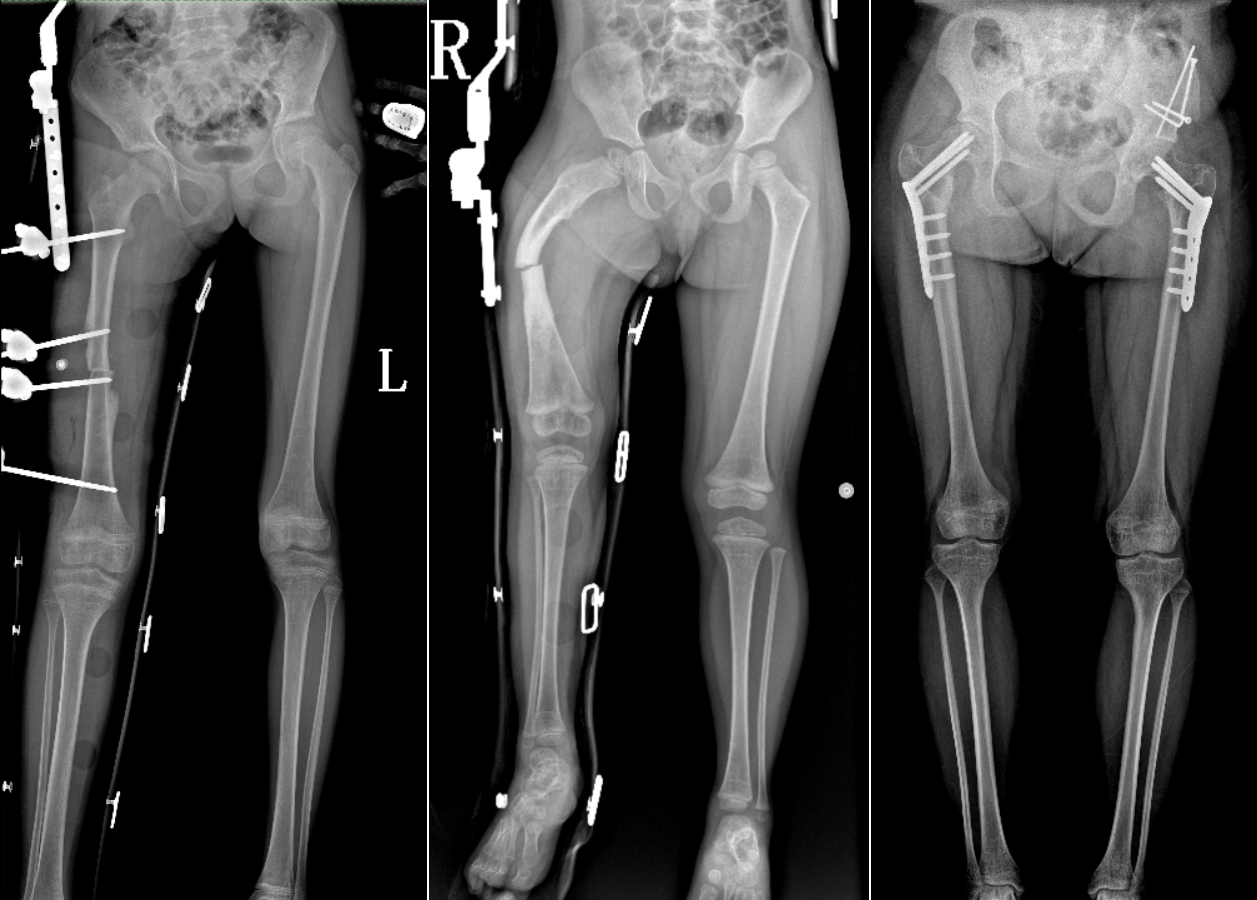

DR是臨床骨科的重要檢查手段之一。在骨科檢查中,脊柱矯形、長(zhǎng)骨骨折、腰椎退行性病變等,需要采集脊柱、下肢全景圖像,輔助醫(yī)生臨床診斷,從而制定科學(xué)的治療方案,普愛(ài)醫(yī)療的大視野平板動(dòng)態(tài)DR就像是一座橋梁,連接起現(xiàn)代醫(yī)療技術(shù)與當(dāng)?shù)厝嗣竦尼t(yī)療需求。

普愛(ài)醫(yī)療自主研發(fā)的大視野平板動(dòng)態(tài),采用17"*34"的有效視野,一次曝光即可得到全脊柱或全下肢影像。相較于多張攝影再軟件拼接的DR設(shè)備,PLX8600解決了拼接圖像存在密度不均勻,拼接處圖像配準(zhǔn)和放大效應(yīng)等問(wèn)題,給臨床帶來(lái)了真正的大視野影像解決方案。

除了常規(guī)靜態(tài)攝影外,PLX8600的大平板具備動(dòng)態(tài)透視和點(diǎn)片功能,能夠很好地觀察復(fù)雜部位病灶,有效地抓取關(guān)鍵幀,降低患者多次攝片的概率。如:全脊柱狀態(tài)評(píng)估、長(zhǎng)骨關(guān)節(jié)活動(dòng)度、下肢靜脈造影瓣膜功能評(píng)估、消化道功能評(píng)估、脊髓造影等更多大視野臨床應(yīng)用,“多面手”都能輕松應(yīng)對(duì)。